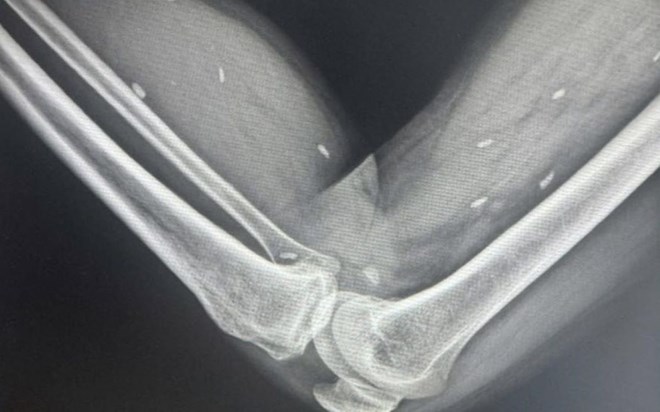

Nhiễm kén sán ở vùng đùi và cẳng chân của bệnh nhân tại Quảng Trị

Quảng Trị - Bệnh nhân nhập viện trong tình trạng đau nhức kéo dài, qua chụp X-quang phát hiện nhiều kén sán rải rác ở vùng đùi và cẳng chân.

Sau thăm khám lâm sàng, bác sĩ chỉ định chụp X-quang thường quy. Kết quả cho thấy hình ảnh nhiều kén sán kích thước nhỏ, dạng hạt gạo, nằm rải rác trong các mô vùng xương đùi và cẳng chân.